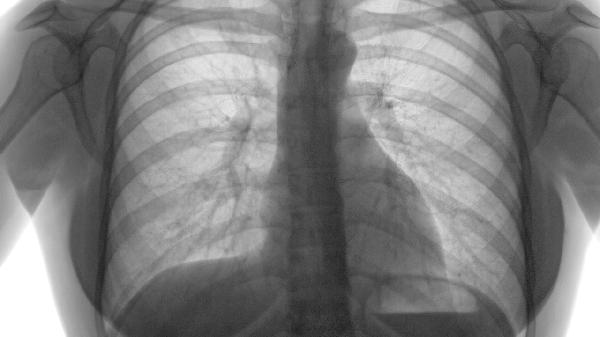

5、定期随访和监测病情是长期管理的关键。患者应定期进行肺功能检查、胸部影像学检查,以及血氧饱和度监测,及时调整治疗方案,预防急性加重。